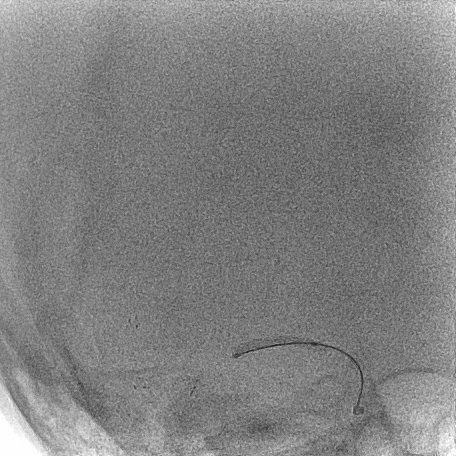

建立通路:

泥鳅塑型,携带125cm长SIM2进入右颈总。

5.5F IntroSky X导管鞘顺利绕过迂曲段进入颈总动脉。

通路尽量高到位,同时注意避免血管痉挛、血流阻断。